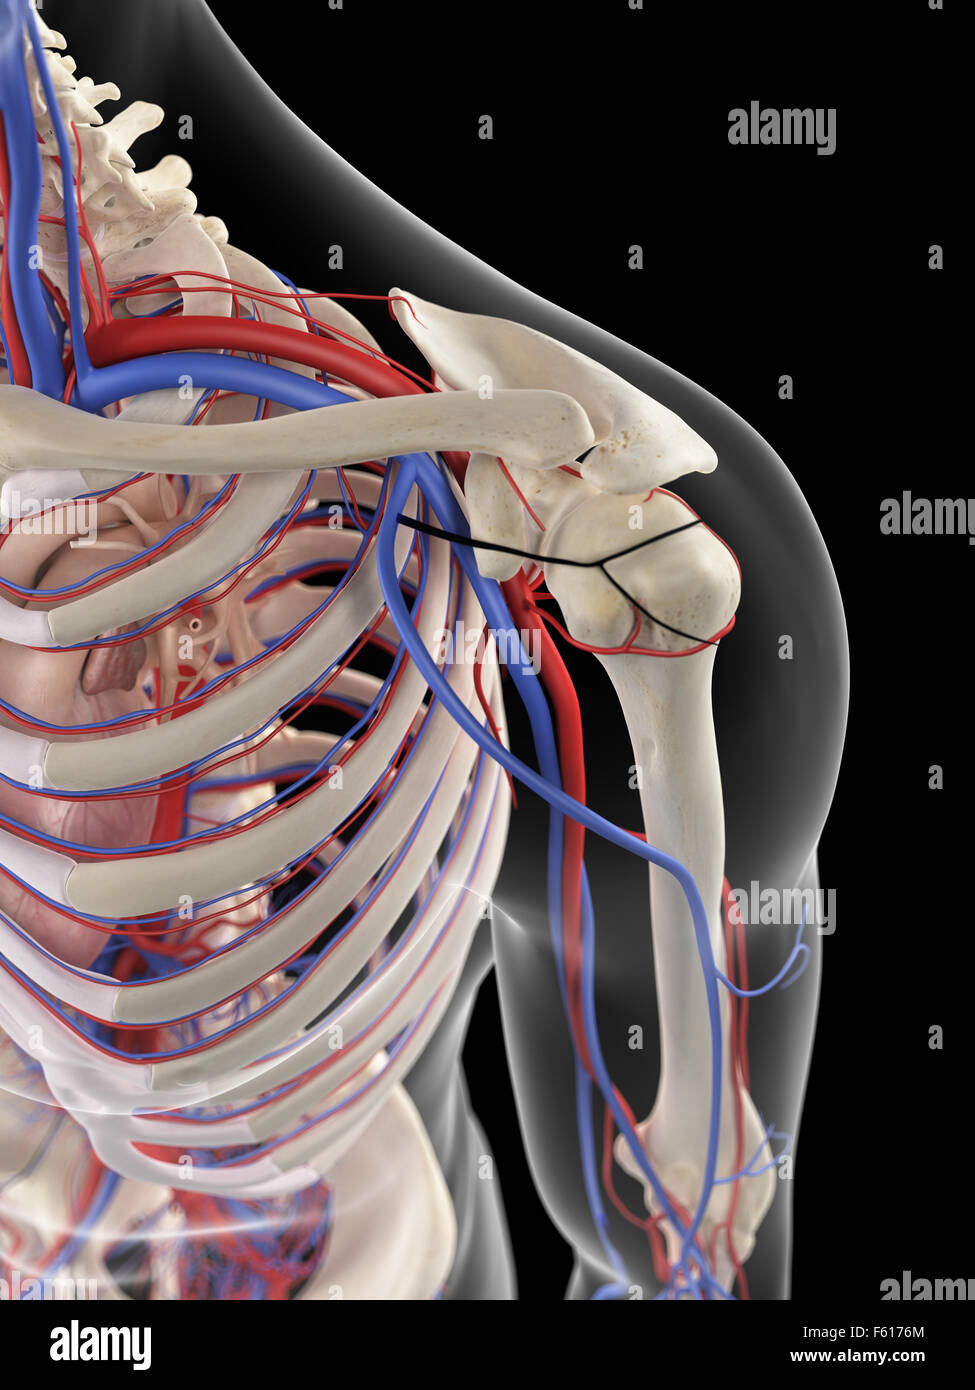

RMETMN27–Darstellung der Blutversorgung und Skelett-Struktur der Unterschenkel, durch die Haut sichtbar.

RMETMNMF–Darstellung der Blutversorgung und Skelettsystem an den Unterschenkeln, durch die Haut sichtbar.

RMETMP9E–Darstellung der Blutversorgung und Skelett-Struktur der Unterschenkel, durch die Haut sichtbar.